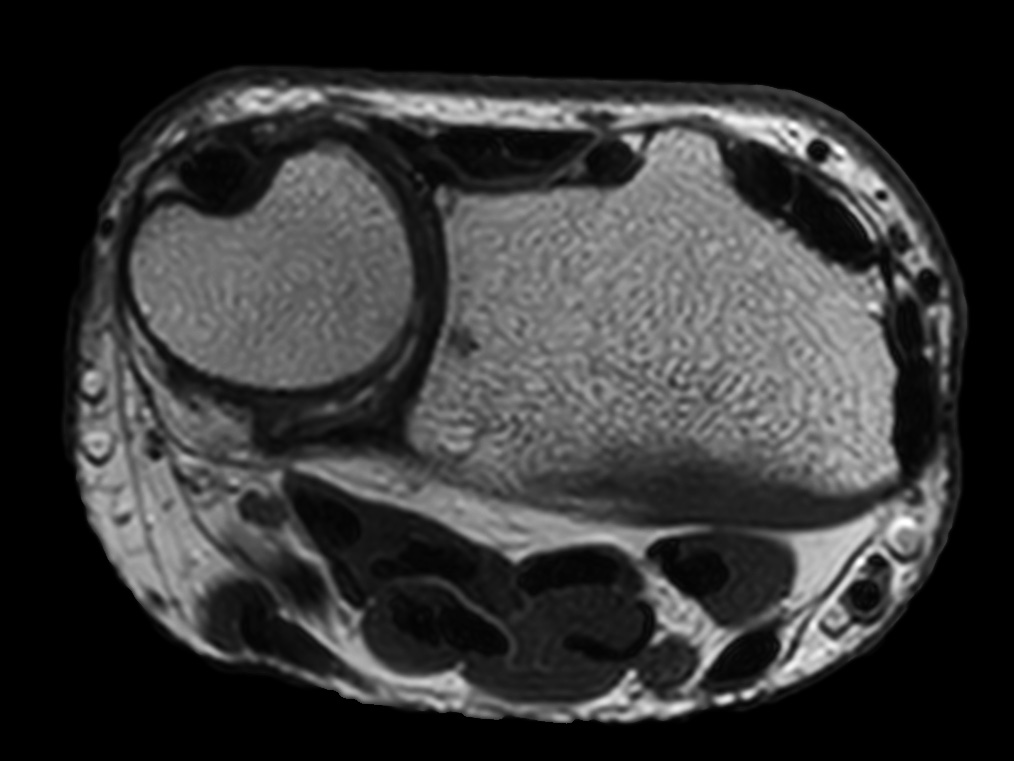

Comprehensive wrist imaging